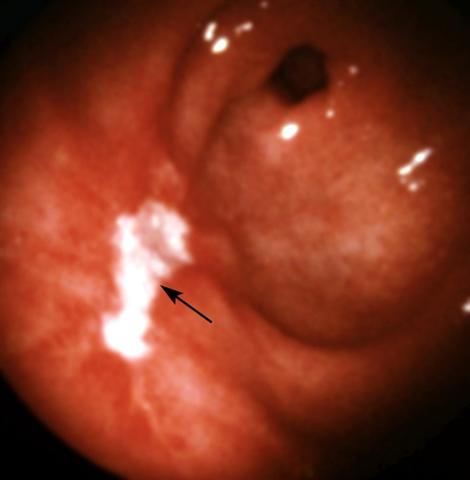

Рис. 9. Эндоскопическая картина желудка в норме и при различных заболеваниях. Язва передней стенки антрального отдела желудка: виден продольный неправильной формы язвенный дефект, покрытый белым фибрином (указан стрелкой); края язвы гиперемированы; отмечается конвергенция складок слизистой оболочки.